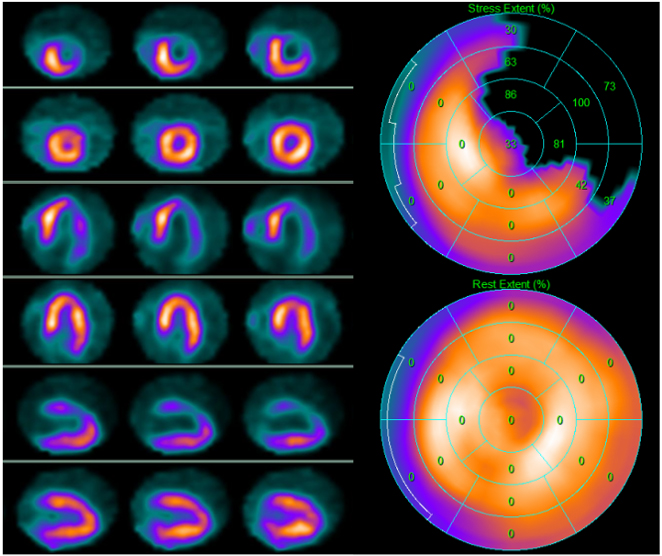

Fig. 1.99mTc-tetrofosmin cardiac SPECT with cadmium, zinc, tellurium (CZT) technology images of a 72-year-old woman with multiple cardiovascular risk factors symptomatic for typical effort angina. Perfusion SPECT revealed a reversible defect in the apex, septal, and anterior walls. Functional data showed an increase in left ventricular end-diastolic volume and end-systolic volume after stress compared to rest (120 versus 114 mL and 80 versus 69 mL, respectively); global systolic function was reduced after stress normal at rest (ejection fraction 40 versus 61%), compatible with myocardial stunning.

Fig. 3.99mTc-tetrofosmin cardiac single photon emission computed tomography (SPECT) images in a 74-year-old woman with arterial hypertension, diabetes mellitus, and a history of obstructive CAD without myocardial infarction treated with triple coronary artery bypass surgery five years earlier. Perfusion imaging was ordered to assess ischemia due to persistent atypical angina after medical therapy optimization. SPECT revealed a large reversible defect in the anterior and the lateral walls showing severe myocardial ischemia. Subsequent angiography revealed complete occlusion of the left main artery, occlusion of the saphenous vein graft anastomosed to the diagonal branch of the left anterior descendent coronary artery, and patency of the other two bypass grafts. Medical therapy was optimized. Left side top row: stress-rest short axis; stress-rest horizontal long axis; stress-rest vertical long axis; right side: polar map of stress (upper image) and rest perfusion (lower image).